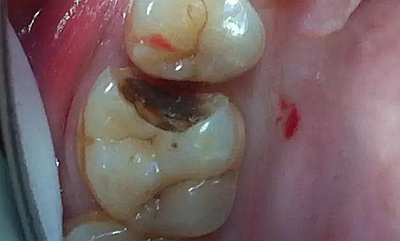

最后附幾例一次性根管治療+冠延長手術+高嵌體修復的病例,均為兩次完成。第一次就診:根管治療一次完成,后冠延長手術,然后高嵌體預備,取模,第二次就診,拆線,試戴嵌體。具體在此不做詳細說明,圖中有詳解。

病例3

該病例后期樹脂嵌體完成,為學生完成。沒有完成后的樹脂嵌體照片。病例已經(jīng)完成。